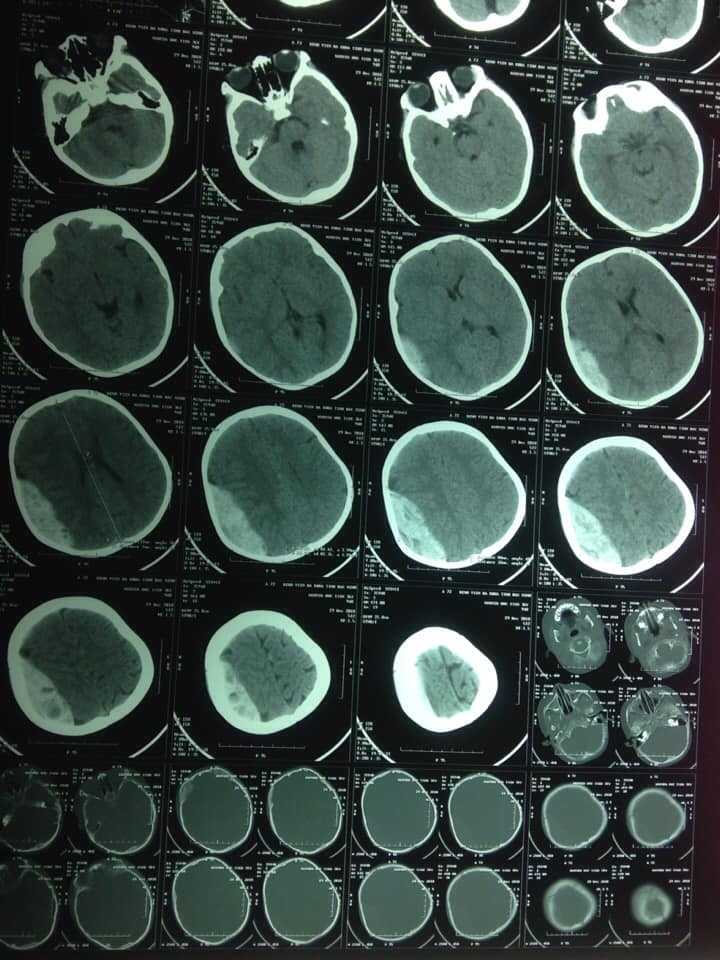

Ngày 29/12/2018, các bác sỹ trực tại khoa Ngoại thần kinh - Lồng ngực kết hợp với kíp gây mê của khoa Phẫu thuật - Gây mê hồi sức, Bệnh viện đa khoa tỉnh Bắc Ninh đã kịp thời cứu sống một bệnh nhân nhi 36 tháng tuổi đến viện sau khi ngã ở nhà với chẩn đoán: chấn thương sọ não tụ máu ngoài màng cứng lớn vùng thái dương đỉnh bên phải. Bệnh nhi Nguyễn Tiến Đ, 36 tháng tuổi, quê ở Thanh Khương - Thuận Thành - Bắc Ninh) nhập viện trong tình trạng: trẻ chậm chạp, không nói, bỏ ăn, nôn tăng dần…Trước đó, bố cháu và cháu trượt chân ngã ở sân nhà. Ngay khi bệnh nhi nhập viện chúng tôi thấy trẻ chậm chạp, không nói, chỉ khóc yếu, tự thở đều, không có liệt chân tay, đồng tử 2 bên đều, phản xạ ánh sáng còn tốt. Các bác sĩ cho bệnh nhi dùng thuốc, thở oxy, làm xét nghiệm và chụp cắt lớp vi tính sọ não cấp cứu, phát hiện thấy một khối máu tụ ngoài màng cứng lớn vùng thái dương đỉnh bên phải là nguyên nhân gây nên các triệu chứng lâm sàng của bệnh nhi.

![]() Hình ảnh phim cắt lớp vi tính sọ trước phẫu thuật |